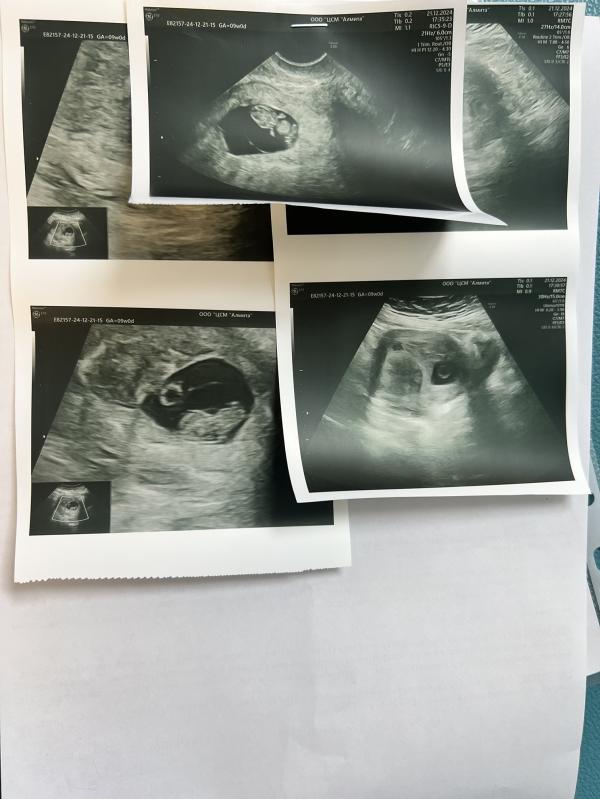

Вчера я решила сделать еще раз узи у другого доктора. Ни чего обнадеживающего он не сказал. Заключение: Маточная беременность соответствует сроку 8 - 9 недель. Миома тела матки малых размеров.

Рубцовые изменения на матке после операции кесарева сечения (тонкий неполноценный рубец). Предлежание хориона, высокий риск по Placenta accreta. Укорочение шейки матки. Несвежая отслойка плодного яйца. УСВ.

Фото моего маленького пупсика для вас. Порадуйтесь и вы за эту кроху.. Позирует 😀

Подождите, не поняла, как на сроке 8-9 недель можно расшевелить ребёнка? По фото как будто недель 13..

Очень просто)) он уже шевелится) и в заключении узи прописано, шевеления плода есть.

Божечки, какая прелесть) уже ручки и ножки видно🙂